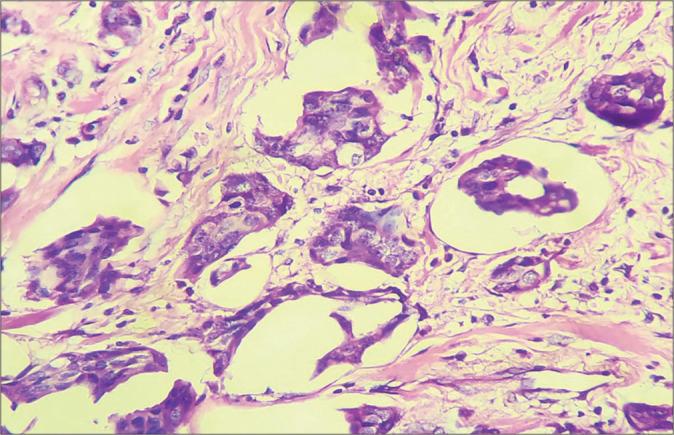

A diagnostic challenge in a rare variant of invasive breast carcinoma - How far one can go.

Cytojournal. 2022 Jun 7;19:35. doi: 10.25259/Cytojournal_26_2021. eCollection 2022.

Invasive Cystic Hypersecretory Carcinoma of Breast: A Rare and Under Diagnosed Variant of Ductal Carcinoma.乳腺浸润性囊性高分泌性癌:一种罕见且诊断不足的导管癌变异型

lnvasive cystic hypersecretory carcinoma of the breast associated with papillary pattern: a rare and poorly recognised variant of ductal carcinoma of the breast.伴有乳头样结构的乳腺浸润性囊性高分泌性癌:一种罕见且认识不足的乳腺导管癌变体。

Invasive micropapillary mucinous carcinoma of the breast is associated with poor prognosis.